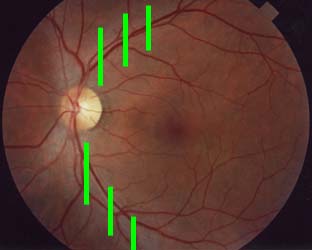

Nervová vlákna

Jsme schopni sledovat vrstvu nervových vláken v každodenní praxi bez nákladných přístrojů? Ano!

Vyšetření vrstvy nervových vláken indirektní biomikroskopií

- štěrbinová lampa s paprskem rovnoběžným s osou našeho pohledu

- 60-90 D čočka nebo čočka Goldmanova

- Pacient v mydriáze

Na snímku vidíme nastavení ramene štěrbinové lampy rovnoběžně s osou našeho pohledu. Pacient se dívá druhým okem 15 stupňů směrem temporálně.